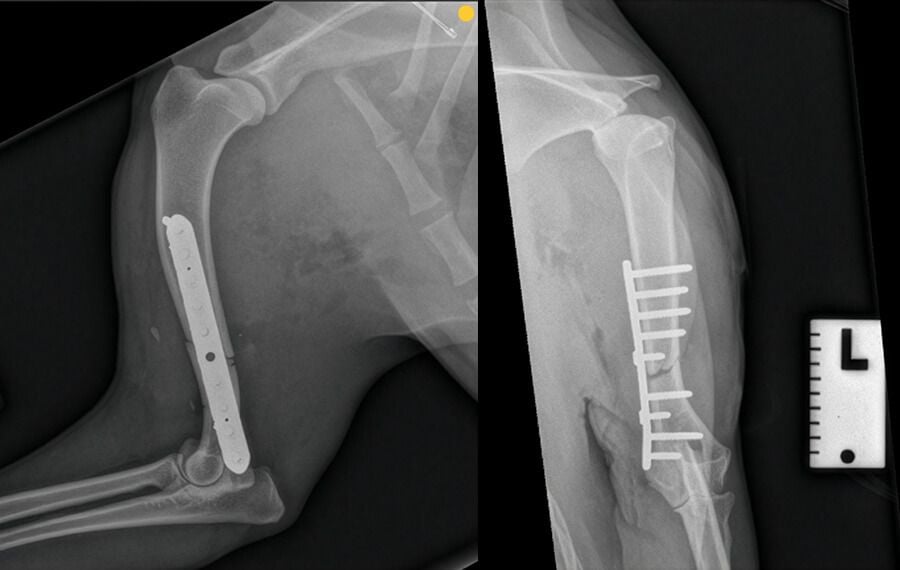

By using internal hardware such as bone plates, screws, or interlocking nails, we can achieve:

Millimetre Precision

We can align the bone perfectly when necessar, which is critical for fractures involving joints to prevent future arthritis.

Increased Stability

Surgery stops the painful "grating" of bone ends and provides immediate support while allowing the tissues to heal.

Earlier Mobility

Internal fixation allows your pet to begin gentle weight-bearing sooner than they could in a restrictive cast.

Our surgical theatres are state-of-the-art and include intraoperative fluoroscopy (a moving X-ray). This allows our surgeons to see exactly what is happening within the bone in real-time, ensuring implants are placed with absolute precision. Furthermore, a specialist anaesthetist oversees every procedure, providing a level of safety not commonly found in general practice.